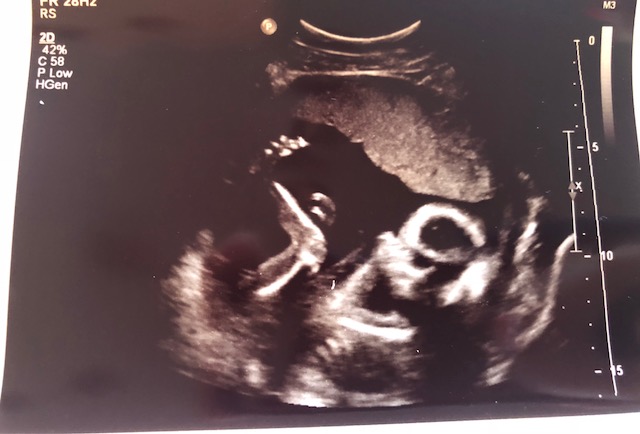

BOY OR GIRL??? Opinions please and why! Thank you! Attachment 40030

I"m afraid this pic is not good for guessing. Baby is SOOO curled up!